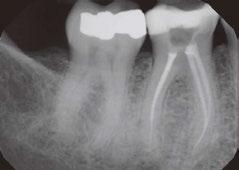

Figures 1A-1B: Two periapical radiographs of tooth No. 24 taken at different angles. Resorptive defect changes position relative to root canal, which according to buccal object rule, means defect is separate from canal and, hence, external to canal

While external root resorption comes in many forms, such as transient surface resorption, pressure resorption, external inflammatory root resorption, invasive cervical root resorption, and replacement resorption (ankylosis), internal root resorption is uniquely different. The differential diagnosis is made by taking multiple radiographs at different angles.9,10 Utilizing the buccal object rule, a lesion of internal origin will remain close to the canal regardless of the angle, while a lesion of external origin will move away from the canal depending on the angle of the radiograph (Figures 1A and 1B).

Additionally, with IRR, the outline of the root canal is usually distorted and appears contiguous with the resorptive defect, while with external resorption, the root canal outline appears normal and can usually be seen running through the radiolucent resorptive defect, as there remains a thin layer of dentin separating the canal from the resorptive area9-10 (Figures 2A-2D).